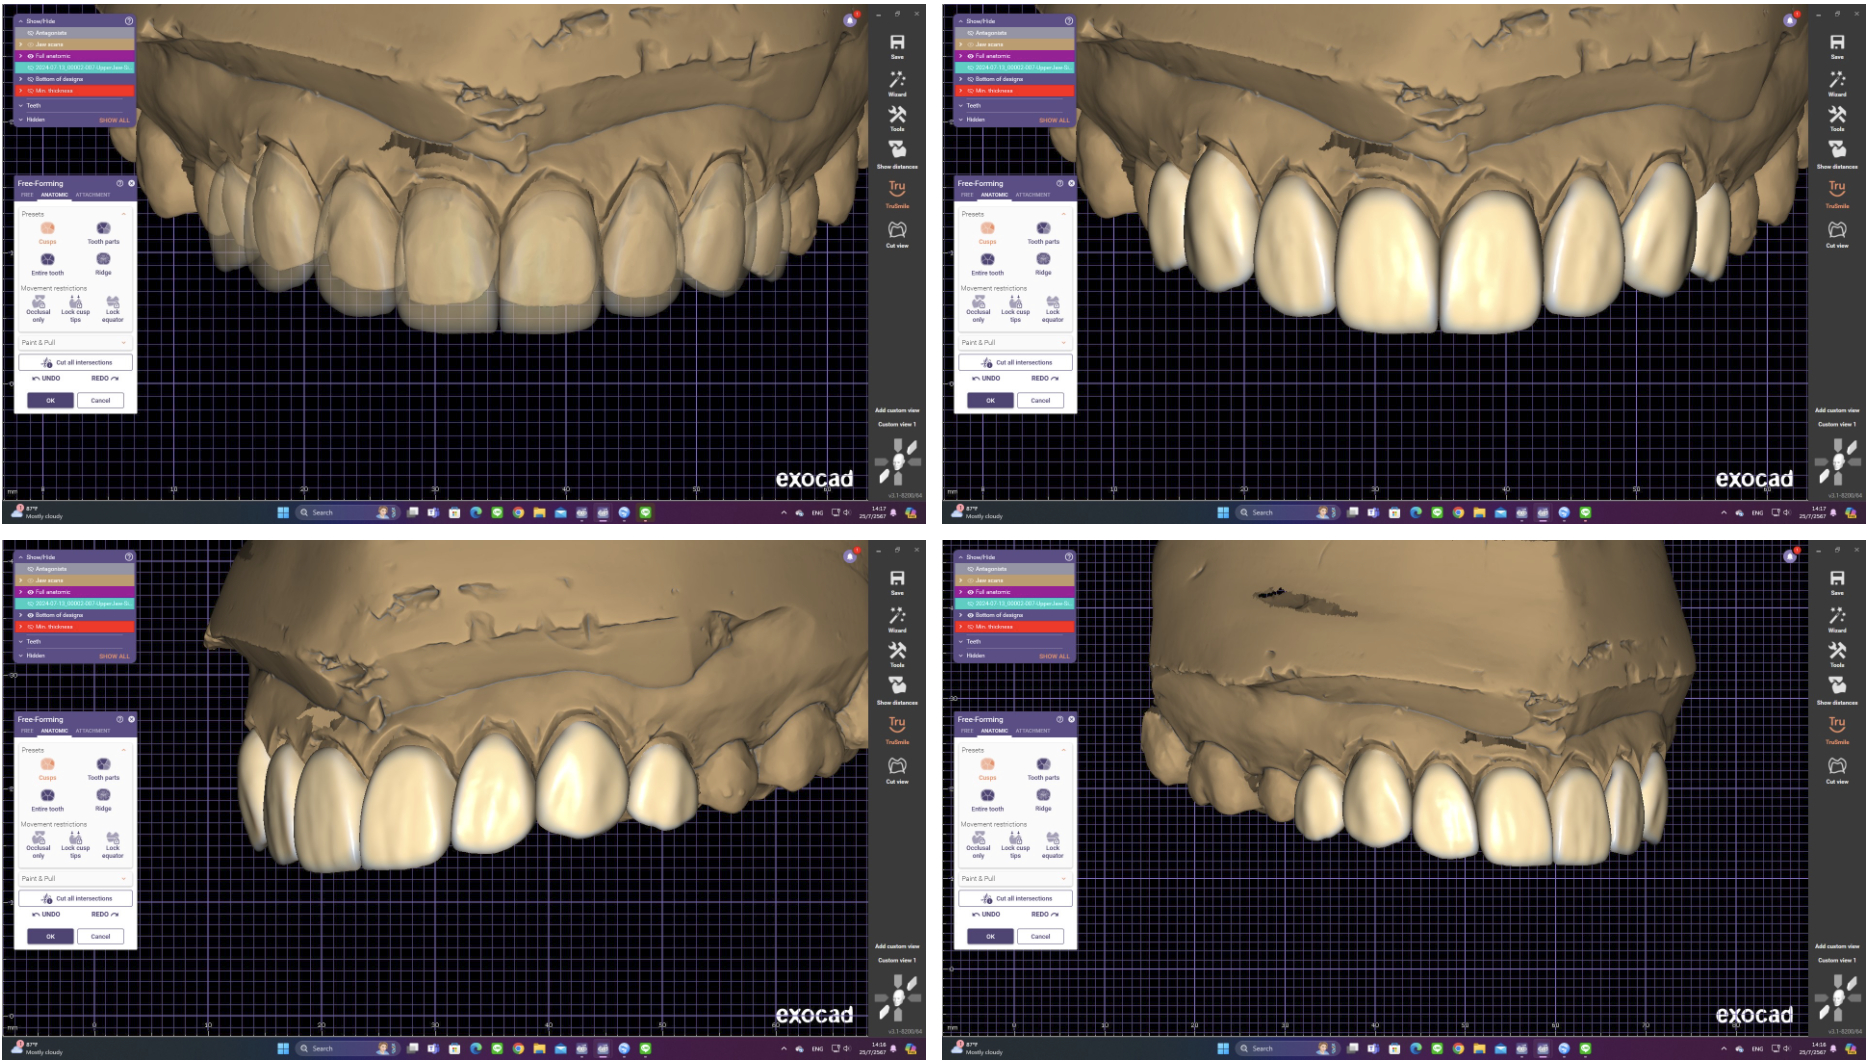

2. Digital Smile Design (DSD)

Using advanced digital imaging and facial analysis, we simulate your new smile before treatment.

This allows:

- Accurate planning

- Predictable outcomes

- A smile that aligns perfectly with your facial features and personality

- 3D scanning or impressions

- Smile design planning